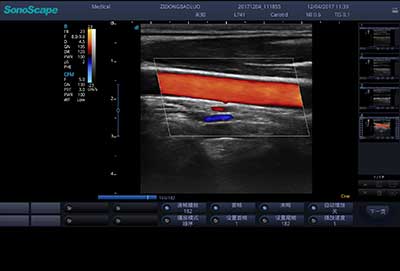

血管内中膜自动测量